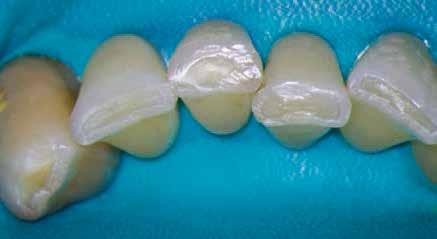

1. a–g. ábrák: A direkt pulpasapkázás lépései. Kiindulási bitewing-felvétel: A meglévő restaurátum közel helyezkedett el a pulpakamrához (a). Kiindulási periapicalis felvétel: Nincs periapicalis elváltozás fennállására utaló jel (b). A pulpaexpozíció (c). A vérzéscsillapítás céljából 20 másodpercen keresztül steril vattagombóccal történő kompressziót követően látható pulpaseb (d). A pulpasapkázás céljából behelyezett anyag, a széli részek tisztázása előtt készült felvétel (e). A röntgenárnyékot nem adó ideiglenes tömés behelyezése után készült felvétel (f). Az első ülés végén a röntgenárnyékot nem adó ideiglenes töméssel ellátott fogról készített röntgenfelvétel (g).

2. ábra: A hat hónapos kontroll alkalmával készített röntgenfelvételen vastag dentinhíd látható a pulpasapkázó anyag alatt.

3. ábra: A hároméves kontroll alkalmával készített röntgenfelvételen megfigyelhető a restaurátum pontos illeszkedése.

A diagnózisunk reverzibilis pulpitis volt. Periapicalis elváltozás jelenlétét nem vélelmeztük. A fogban lévő amalgámtömés eltávolítása során körülbelül egy 3 mm átmérőjű pulpaseb keletkezett a buccalis pulpaszarvnak megfelelően (1. a–g. ábrák) Mivel nem tapasztaltunk jelentős vérzést, és a diagnózisunk reverzibils pulpitis volt, ezért a direkt pulpasapkázás elvégzése mellett döntöttünk.

A kavitást 2,5%-os nátrium-hipoklorit oldattal fertőtlenítettük, majd sűrű konzisztenciájú kalcium-szilikát alapú anyagot (CeraPutty, Meta Biomed) készítettünk elő a direkt pulpasapkázás elvégzéséhez. Az első kezelés végén röntgenárnyékot nem adó ideiglenes töméssel (NexTemp LC, Meta Biomed) zártuk

az üreget annak érdekében, hogy a direkt pulpasapkázásra használt anyag megfelelő pozícióját radiológiailag ellenőrizni tudjuk. A második ülés során kompozit tömőanyagból (Ezfil, Meta Biomed) direkt adhezív restaurátumot készítettünk.

A kezelést követően a beteg tünetmentes volt. A kérdéses fog a kontrollvizsgálatok során végzett szenzibilitástesztekre fiziológiás reakciókat adott. A hat hónapos kontroll alkalmával készített röntgenfelvételen a sérülésnek megfelelően széles dentinhidat észleltünk (2. ábra). A restaurátum a hároméves kontroll során is megfelelőnek bizonyult (3. ábra)